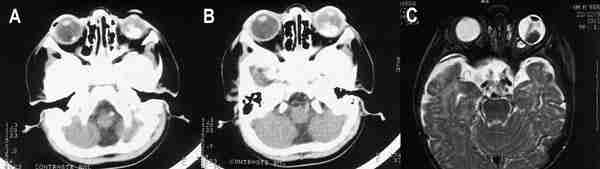

Más del 90% de los RTB muestran calcificación en tomografía computada (TC), generalmente en la porción posterior del globo (4). Su aspecto es variable, única o múltiple, finas o gruesas. Si el tumor es pequeño la calcificación puede ser difícil de identificar (5). La TC permite hacer cortes seriados de 1,5 a 3 mm de espesor o estudiar un volumen orbitario mediante técnica helicoidal. En el estudio con contraste intravenoso el realce tumoral es mínimo o moderado, no obstante puede ayudar a identificar enfermedad retrobulbar e intracraneal aunque para ello es más sensible la resonancia magnética (figuras 2a y 2b).

53-02.jpg (9588 bytes)

Figuras 2a, b y c. Retinoblastomas bilaterales calcificados. Imágenes axiales mediante TC (a, b) y secuencia potenciada en T2 de RM. El calcio se define mejor en el estudio de TC.

La resonancia magnética (RM) muestra menor sensibilidad en la detección de calcio que la US o la TC, sin embargo supera a estas dos técnicas en la valoración de extensión local, diseminación al SNC y en el diagnóstico diferencial con entidades que simulan al RTB (1) (figura 2c). El tumor aparece iso o levemente hiperintenso respecto al vítreo en secuencia eco de espín potenciada en T1 (SET1) en relación a hemorragia intratumoral y al depósito de sustancias paramagnéticas asociadas a calcificaciones tumorales (6) (figura 3). En secuencia eco de espín potenciada en T2 (SET2) la señal del tumor es hipointensa respecto al vítreo. El grado de extensión local se valora tras la administración de gadolinio intravenoso mediante secuencias SET1 con saturación de la grasa. Aunque el realce tumoral es variable, siempre ha de realizarse estudio con contraste ya que ayuda a identificar enfermedad retrobulbar (4).